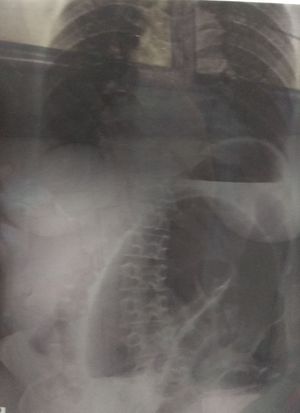

50 years male with pain abdomen and vomiting.. Diagnosis??

Coffe bean appearance (sigmoid volvulus